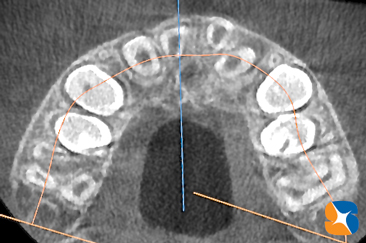

上からの断層で前後の歯並びをチェック

コラム「上からの断層で前後の歯並びをチェック」の画像